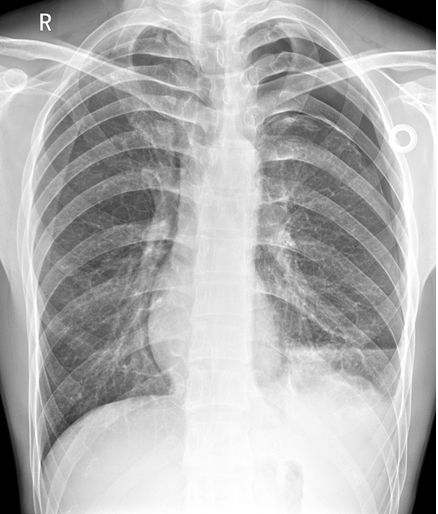

病例1

病例1患者的X线胸片

左上肺肺野可见肺叶压缩带边缘,肺叶压缩约30%(灰色区域)。左下肺野可见液-气平面,约与第5前肋相平(蓝色虚线),肺门影不浓。心影及纵隔向对侧轻度移位。

侧位片可见左侧肋膈角变钝,少量胸腔积液